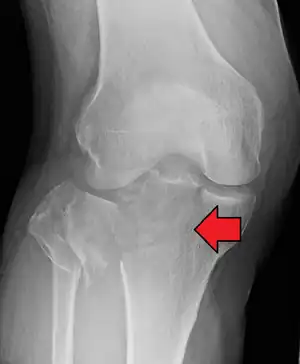

Lipohemarthrosis (presence of fat and blood from bone marrow in the joint space after an intraarticular fracture) seen on X-ray in a person with a subtle tibial plateau fracture

Lipohemarthrosis due to a tibial plateau fracture